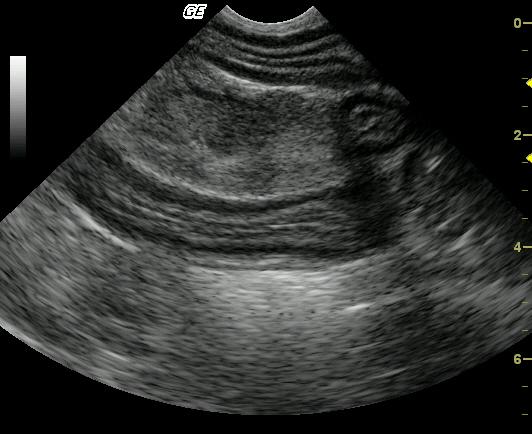

The three segments of bowel included in this image are moderately to markedly thick walled. The intestinal muscularis layer is most severely thickened, occupying approximately 20 to 40% of total wall thickness. Discernible intestinal wall layering is maintained. A markedly enlarged, mildly hypoechoic lymph node is present in the center of the image. The lymph node is coarse and lacks delineation between the echogenic medulla and hypoechoic cortex.

Given the degree of lymph node enlargement, primary consideration is given to neoplasia and lymphosarcoma is primarily suspected. Malignant transformation of chronic inflammatory bowel disease may have occurred. Infiltration with mast cell tumor would be considered less likely.